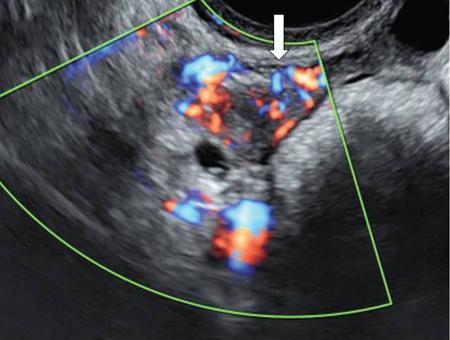

Venkatraman Indiran Bridging vessel sign Multiple vascular channels (white arrows) connecting uterus (black arrow) to an adjacent pelvic mass on imaging studies, is known as the ‘bridging vessel’ or ‘bridging vascular’ sign. Originally described on colour Doppler imaging, but also seen on computed tomography (CT) or magnetic resonance imaging (MRI). Helps in differentiating a mass of uterine origin, typically a subserosal fibroid, from other pelvic masses. Sensitivity and specificity of ‘bridging vessel sign’ in identifying subserosal fibroids range from 90% to 100%. (Best seen when subserosal fibroid is larger than 3 cm in diameter.) Ovarian masses invading the uterus may rarely produce a falsely positive bridging vessel sign. Broccoli sign Submucosal uterine leiomyoma prolapsing into the endocervical canal, along with its stalk in the uterine cavity on sagittal T2-weighted images together is called as ‘broccoli sign’ (white arrow). Submucosal uterine leiomyoma Bunch of grapes Intrauterine mass with cystic spaces without any associated foetal parts on ultrasound (white arrows) classically gives a ‘snow storm’ or ‘bunch of grapes’ appearance. Complete hydatidiform mole Hourglass sign Deep infiltrating endometriosis (DIE) affecting the posterior urinary bladder wall, usually in the midline, causes loss of its distensibility, resulting an hourglass configuration of urinary bladder. Deep infiltrating endometriosis (DIE) Hyperechoic line sign Normal endometrium surrounding the endometrial polyp on ultrasound appear as a hyperechoic rim on transvaginal ultrasound is called as ‘hyperechoic line sign’. Hyperechoic line sign represents a focal intracavitary lesion. Endometrial polyp Indian head dress sign/moose antler sign In deep infiltrating endometriosis (DIE), adhesions between the anterior wall of rectosigmoid and posterior wall of uterus, stretches the muscular layer of the bowel and creates an infiltrative nodule with parallel lines that extend from the adhesion to the rectosigmoid. This is called as ‘Indian head dress sign/moose antler sign’ (white arrow). This is seen on sagittal T2-weighted images as well as transvaginal ultrasound. Deep infiltrating endometriosis (DIE) Interstitial line sign An echogenic line that extends into the upper regions of the uterine horn and borders the margin of the intramural gestational sac is called as the ‘interstitial line sign’ (white arrow). Seen best on transabdominal/transvaginal ultrasound. Specific finding of interstitial pregnancy Mushroom cap sign Mushroom-shaped lesion which is seen displaced into the bowel lumen in patients with solid invasive endometriosis of the rectosigmoid colon on axial or sagittal T2-weighted MRI is called as ‘mushroom cap sign’ (red box and white arrow). Low signal intensity base of the mushroom corresponds to hypertrophy and fibrosis of the muscularis propria, whereas the high intensity cap represents oedematous mucosa and submucosa. Deep infiltrating endometriosis (DIE) Pedicle artery sign Feeding vessel sign Central vessel entering the endometrium from the surrounding myometrium colour Doppler imaging of the endometrium in endometrial polyps is called as pedicle artery sign (white arrow). Endometrial polyps in women with postmenopausal bleeding. (Sensitivity of 76.5%; specificity of 95.3%.) Popcorn ball calcification Dense, amorphous calcifications of uterine fibroids seen on the plain radiographs is called as ‘popcorn calcification’ (white arrow). Confluent, coarse calcification constitutes the most specific radiographic sign of a benign uterine fibroid; but only 10% or fewer of fibroids show calcification. Question mark sign of uterus The uterine corpus that is flexed backward with the fundus of the uterus facing the posterior pelvic compartment and the cervix directed anteriorly toward the urinary bladder, is called as question mark sign of uterus (white arrow). Also called as comma-shaped uterus. 93% specificity and 75% sensitivity in diagnosing adenomyosis uterus. Sliding organs’ sign When the uterus and ovaries glide freely over the posterior and anterior organs (such as rectum and urinary bladder, respectively) during real-time dynamic transvaginal sonography, it is called as ‘positive sliding organs’ sign’. In case of adhesions due to endometriosis, free gliding of organs is absent and is called as negative sliding sign. Snowstorm sign Grainy appearance with low-level homogeneous internal echoes which move slowly downward due to their viscosity seen in endometrioma on transvaginal ultrasound is called as snowstorm sign. Endometriomas Split fibre sign Presence of curvilinear T2 hypointense strands within the degenerated leiomyoma separated by the fluid accumulation and oedema is called as the ‘split fibre’ sign. Split fibre sign on T2-weighted MRI can be used to differentiate hydropic degeneration from other conditions like malignant change. Three-line sign or triple line sign or trilaminar appearance Shortly before ovulation, two additional bright linear echoes outline two hypoechoic layers of endometrium with a central hyperechoic line in the endometrium (white arrow). It is called as the ‘three-line sign’ or ‘triple line sign’ or trilaminar appearance. A triple-line pattern with a moderate endometrial thickness is associated with a good clinical outcome on in-vitro fertilization. Venetian blind shadowing Also known as ‘rain shower’ appearance Heterogeneous myometrial appearance due to hyperechoic heterotopic endometrial tissue and hypoechoic hyperplastic smooth muscle appearing as vertical linear bands of shadows on ultrasound is called as ‘Venetian blind shadowing’. Classically described in uterine adenomyosis; sometimes in uterine fibroids also. Bead on strings sign Thickened endosalpingeal longitudinal folds within a dilated fallopian tube without wall thickening appears as small mural nodules on cross-sectional images on ultrasound is called as ‘bead on strings’ appearance. Seen in chronic salpingitis Beaded tube Multiple constrictions along the course of fallopian tube may form due to scarring is seen in genitourinary tuberculosis and shows a ‘beaded’ appearance. Female genital tuberculosis Cogwheel sign Thickened endosalpingeal longitudinal folds within a dilated fallopian tube with thickened wall appears as small mural nodules on cross-sectional images across the long axis of the fallopian tube on ultrasound (white arrows) produce a characteristic ‘cogwheel’ appearance. Seen in acute salpingitis. The presence of thickened longitudinal folds is pathognomonic for hydrosalpinx. Cobblestone tube Rounded filling defects in cases of fallopian tube tuberculosis are called as the cobblestone pattern. Is an effective radiographic sign of intraluminal scarring and adhesions. Female genital tuberculosis Golf club tube Occlusion of the isthmus or fimbrial end of the fallopian tube and filling up of the tube with serous or clear fluid produces a moderate dilatation at the fimbrial end, produces a ‘golf club–like appearance’. Female genital tuberculosis Halo sign Thin radiolucency seen separating the loculated peritubal collection from the dilated tube, is known as the ‘halo sign’. This radiolucent halo represents the thickened wall of the tube. Female genital tuberculosis Incomplete septation sign Thin linear structures appearing to protrude into the tubular cystic adnexal structures, but not touching the opposite walls is called ‘incomplete septation sign’ of hydrosalpinx. Apparent septae are due to apposition of the inner walls of the dilated and folded fallopian tube. Hydrosalpinx Pipe stem tube Rigid contour of the fallopian tube seen in cases of fallopian tube tuberculosis is called as ‘pipe stem appearance’. Female genital tuberculosis Leash sign Typical eccentric leash of vessels on colour Doppler (white arrow) showing a low resistance placental type of flow on spectral Doppler in fallopian tube ectopic pregnancies is called as leash sign.